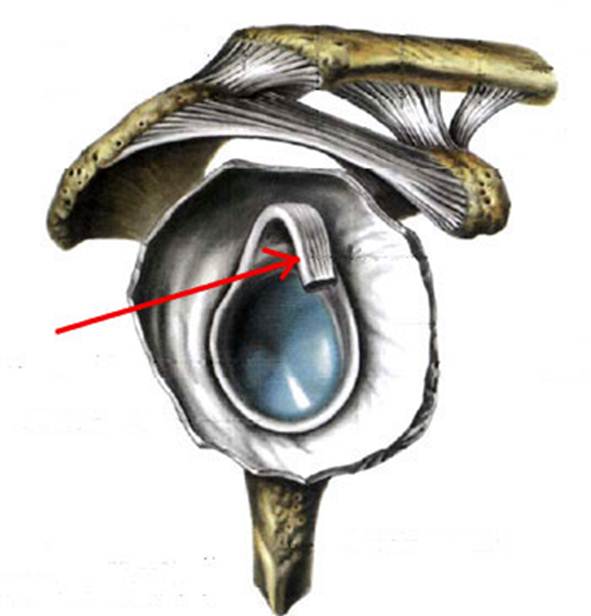

S: Стрелка указывает на art. humeri (латинский язык).

S: Стрелка указывает на tendo m bicipitis brachii

S: Стрелка указывает на lig. coracoacromiale

S: Цифрой 6 обозначена суставная капсула плечевого сустава (русский язык).